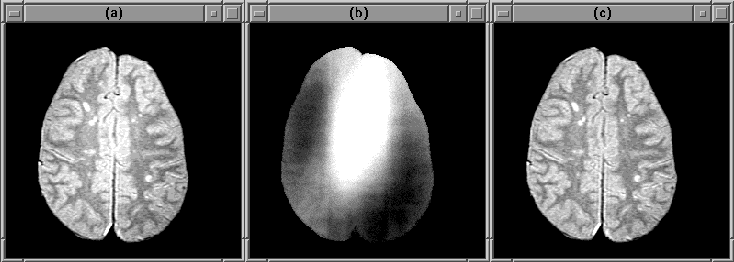

Figure 7.20 shows slice 19 of the PD-weighted Data Set 1 before and after intensity correction. Results, including quantitative measures for several data sets are presented in Chapter 8.

Figure 7.20: An MR image slice (a) before

intensity correction and (c) after. (b) shows the RF inhomogeneity.